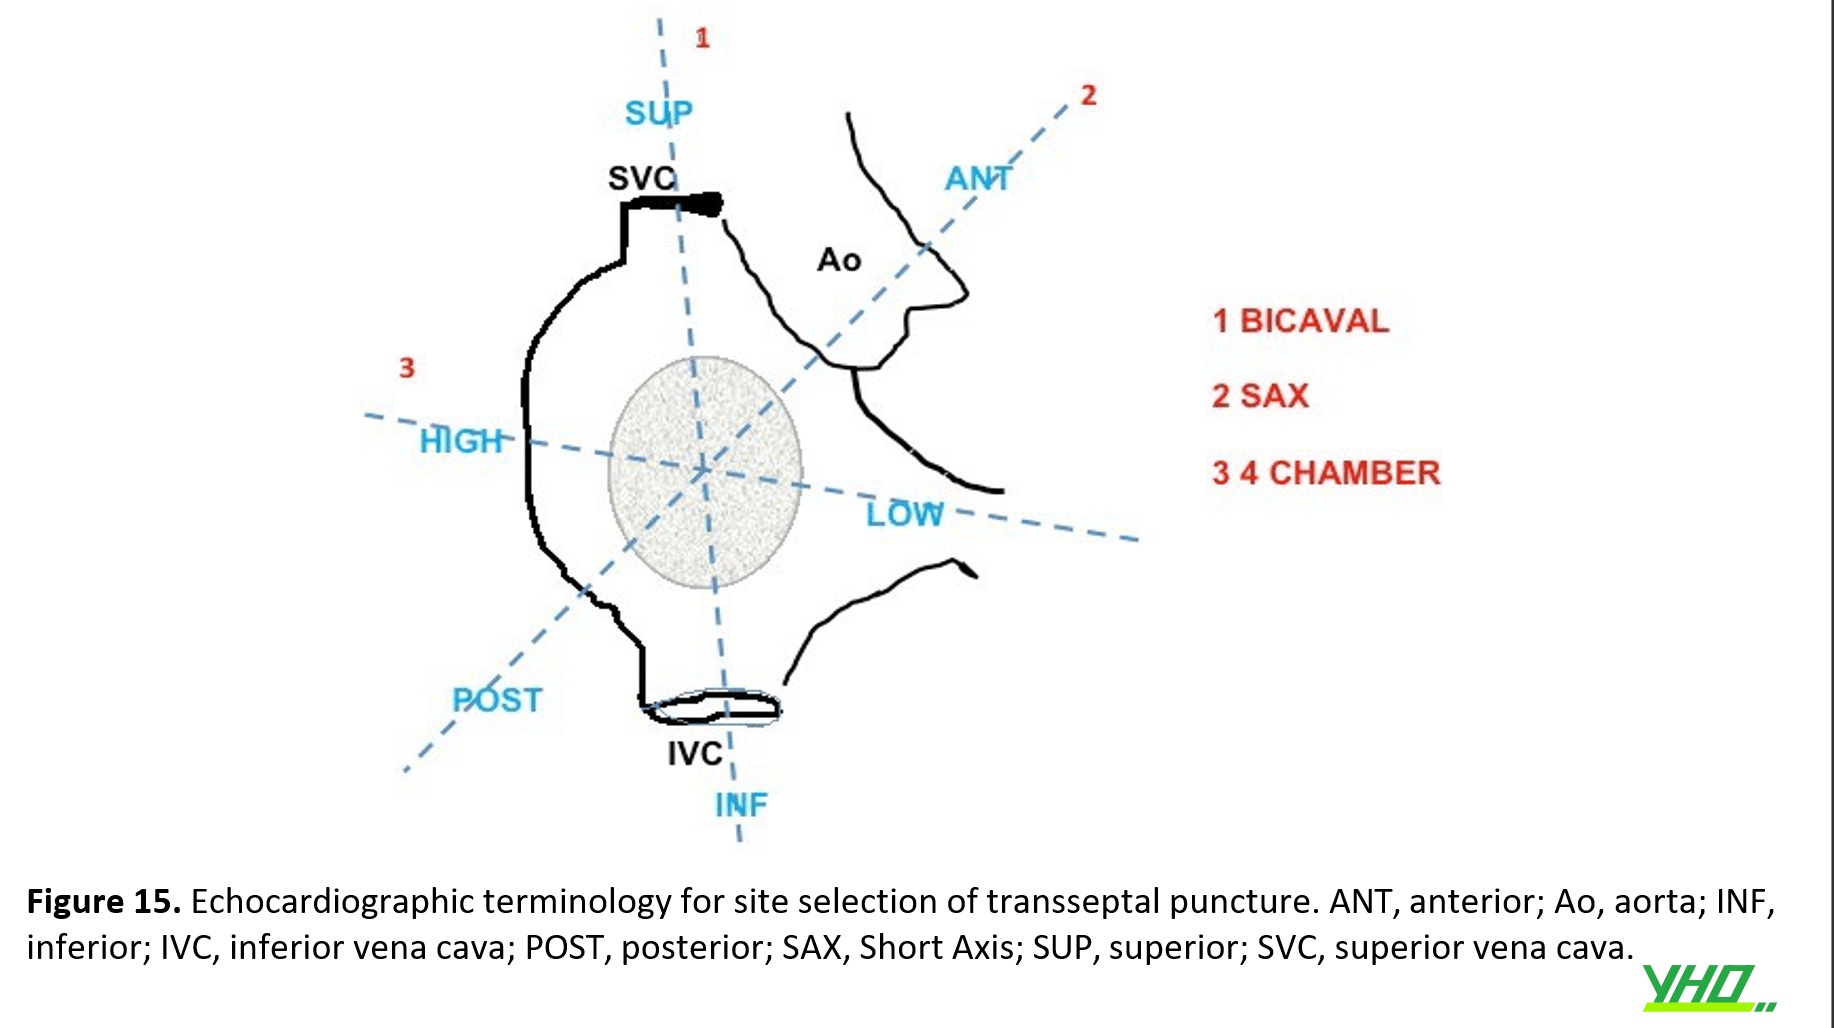

Dù kỹ thuật hình ảnh được sử dụng là gì, nó đòi hỏi sự hiểu biết và hợp tác tốt giữa bác sĩ can thiệp và bác sĩ siêu âm tim, cũng như việc sử dụng các định nghĩa giống nhau, để tối ưu hóa hiệu suất của quy trình.(hình 15)